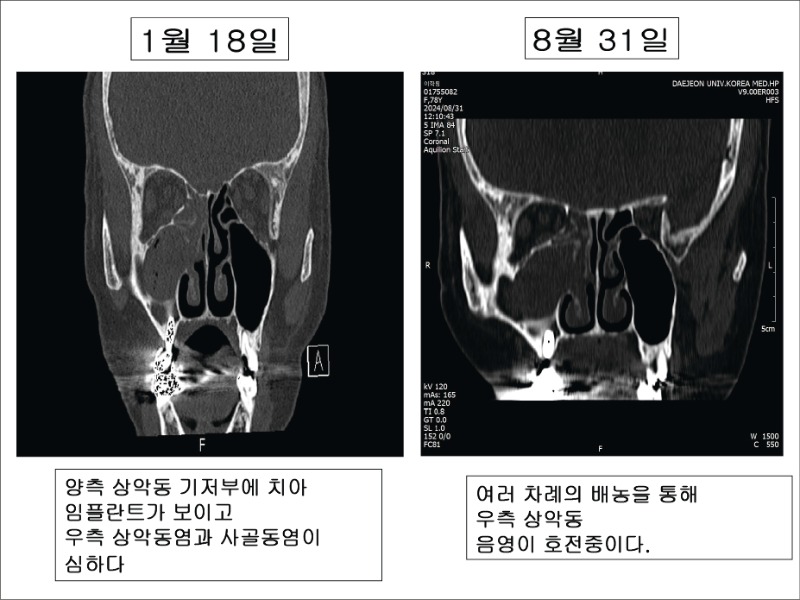

CT 영상에서 부비동저, 치근 주위 변화를 살피는데, 일측성 상악동의 불투명한 음영을 확인하고 특히 임플란트 삽입 후 발생한 경우에는 임플란트 주위의 염증상태를 확인한다.

8월3일 치료 시작 이후 8월20일경부터는 확실히 비루 양이 늘어났고, 20일 전후로 자택에서 티스푼 하나 정도의 밥풀 으깨진 것 같은 냄새가 많이 나는 콧물이 2차례 울컥 나온 뒤 8월31일 이후로는 콧물의 농도가 묽어지고 콧물에서 나는 악취도 거의 없어졌다고 한다. 더불어 오랜 기간 맛이 이상하게 느껴지던 증상도 호전 중이다.

8월31일에 중간 과정을 살피기 위해 PNS CT 촬영을 의뢰했고, 1월 영상과 비교해본 결과 아직 농은 잔존하고 있지만 줄어든 결과가 나와 차후 한달간 더 치료를 하기로 보호자와도 상의했다.